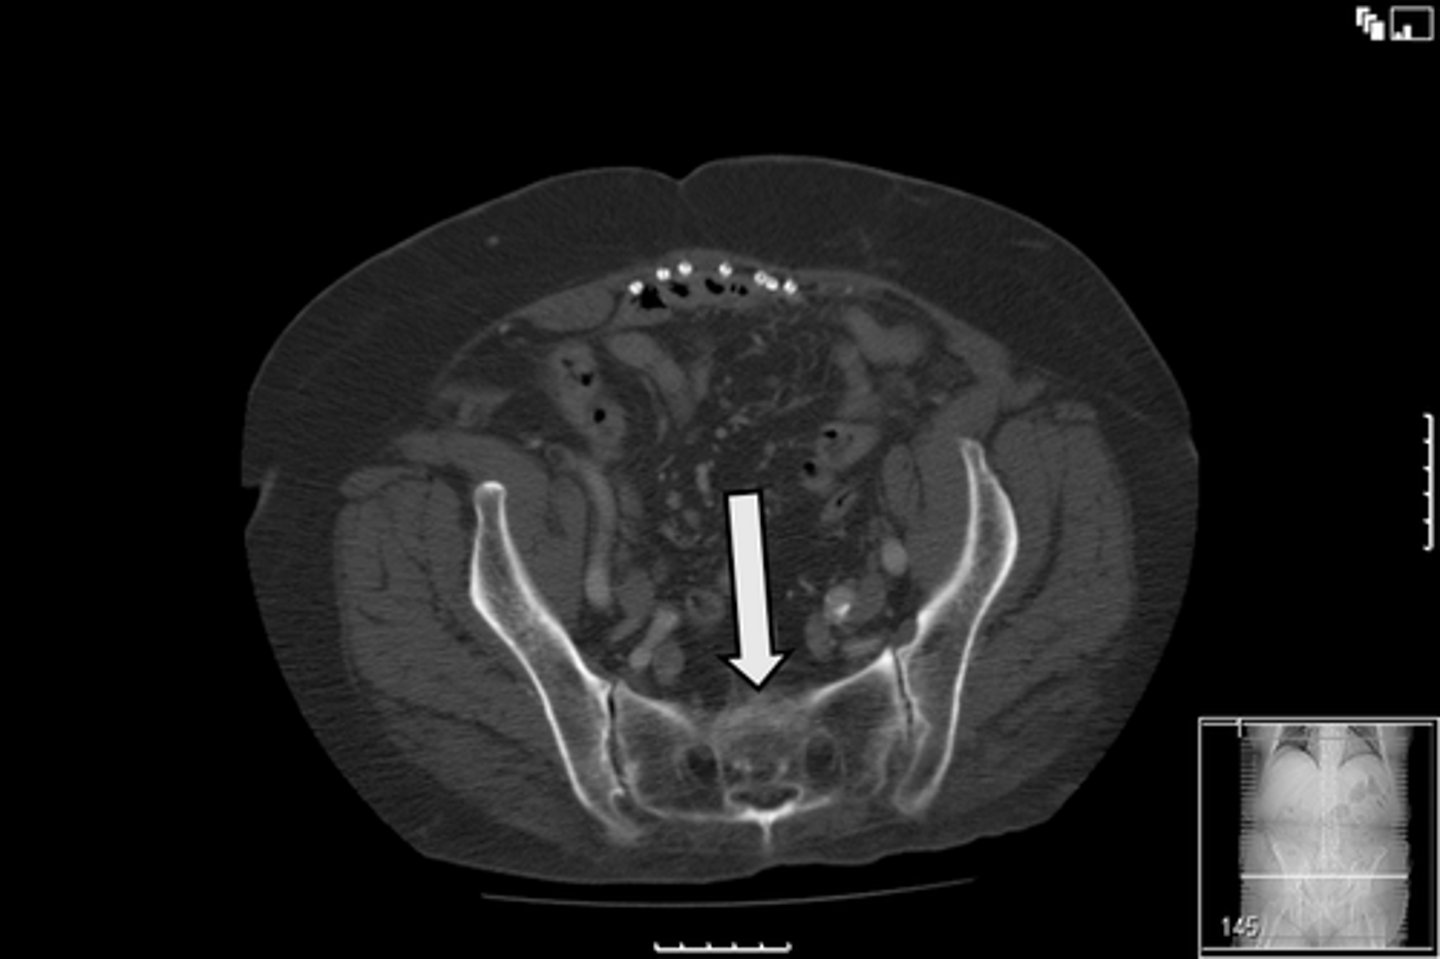

Sacrum

What is indicated in the image?

<p>What is indicated in the image?</p>

15

New cards

AP pelvis

What is the image?

<p>What is the image?</p>

16